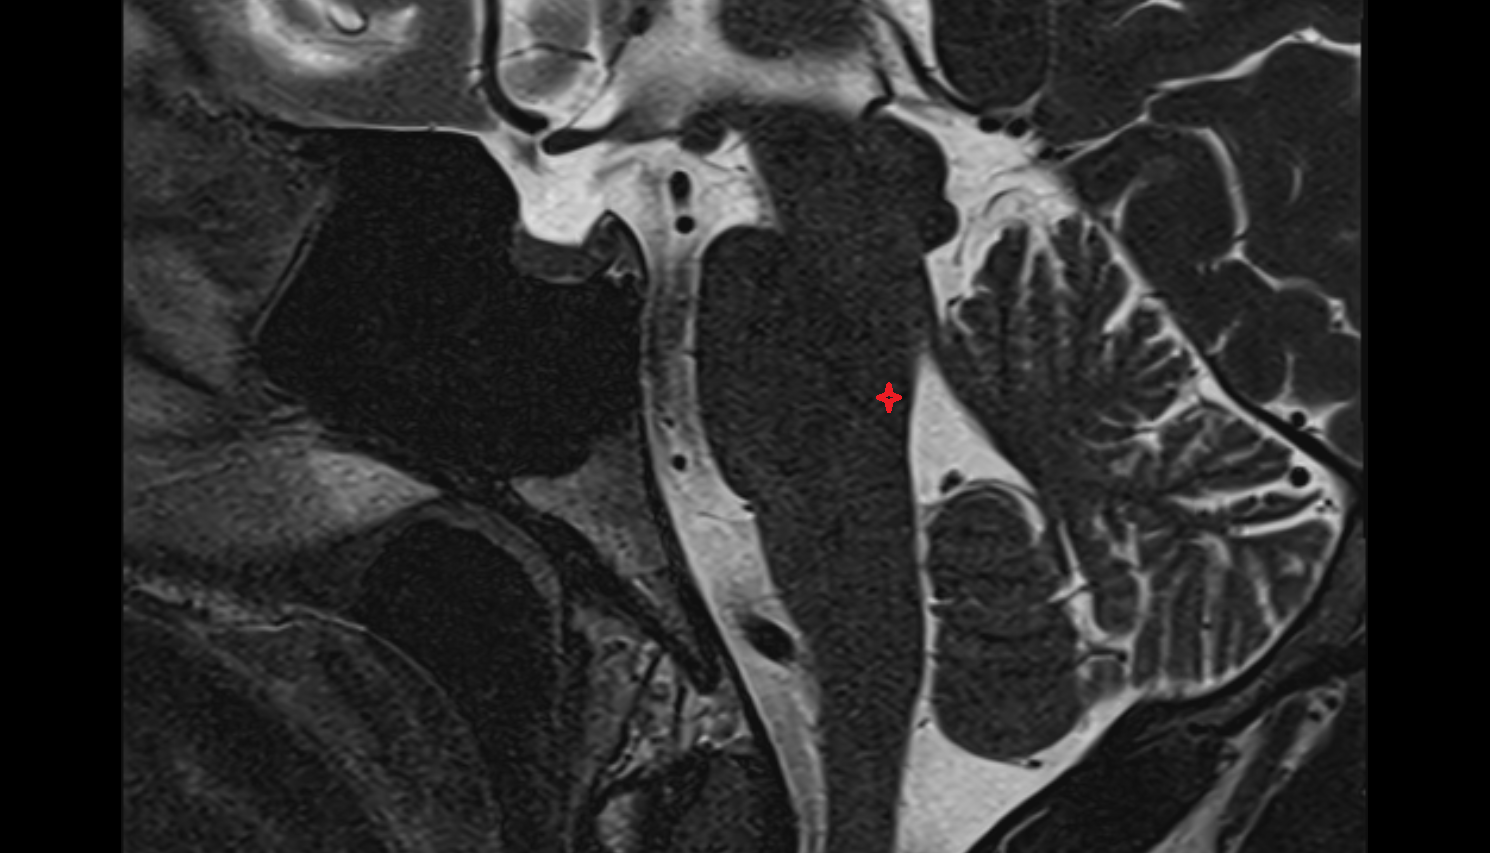

- Posterior cerebellomedullary cistern (cisterna magna)

- Cisterna magna

- Premedullary cistern

- Median aperture of fourth ventricle (foramen of Magendie)

- Lateral aperture of fourth ventricle (foramen of Luschka)

- Posterior inferior cerebellar artery

- Cerebellar tonsil (H IX)